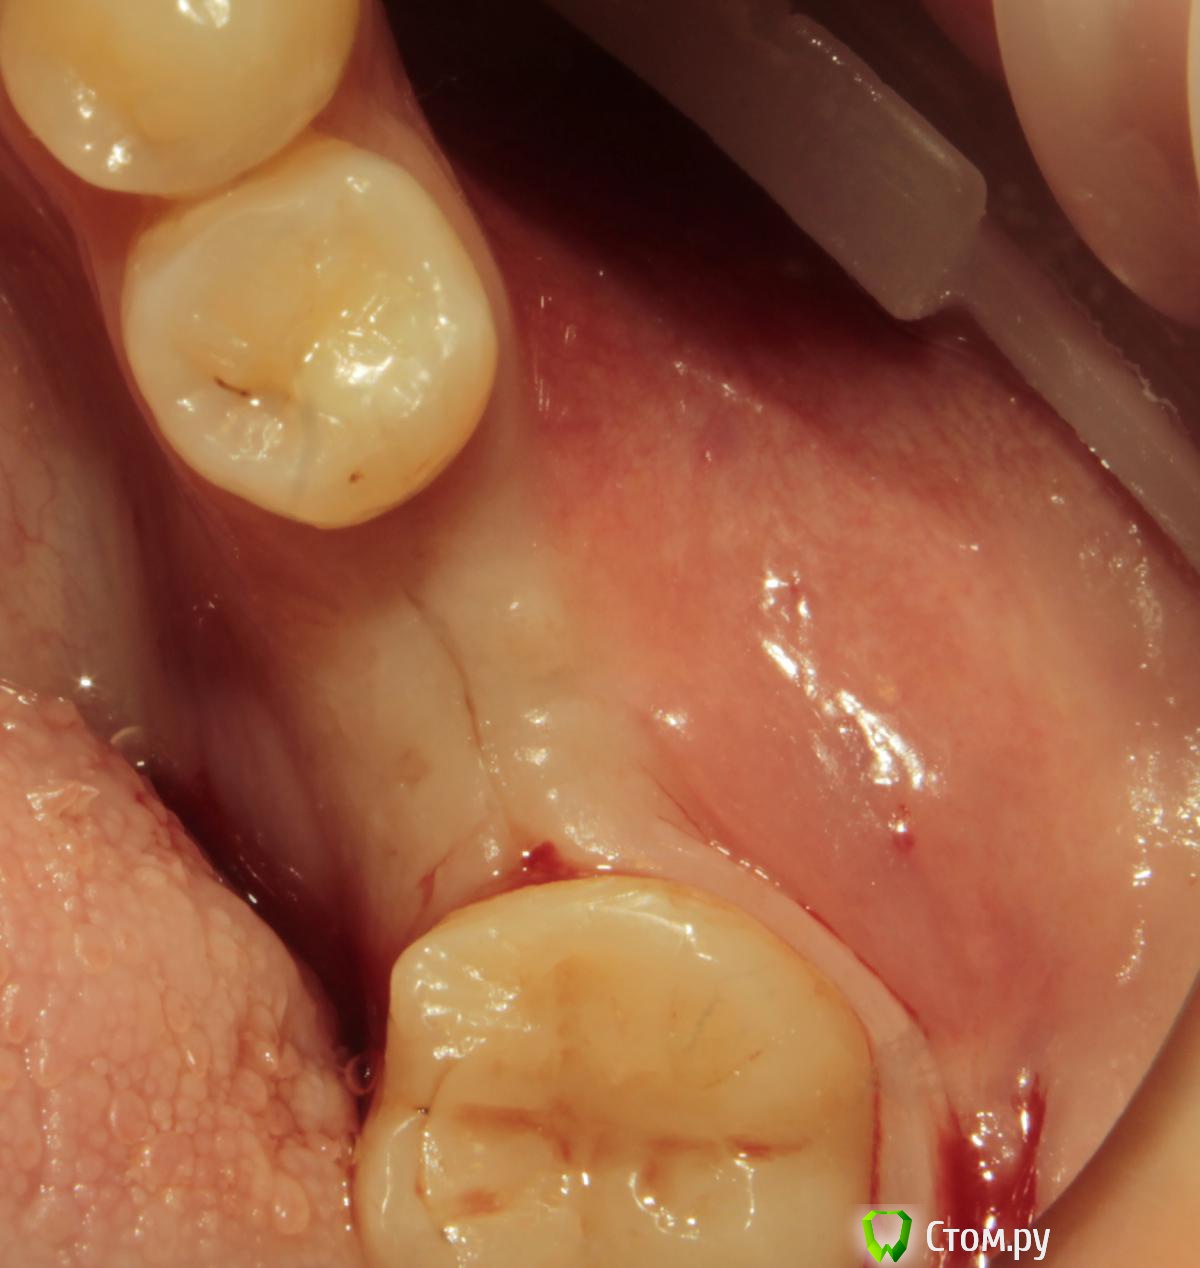

Acidrocker Опубликовано 13 мая, 2014 Поделиться Опубликовано 13 мая, 2014 Вот такой круассан получил на днях. На раскрытии имплантата под расщепленный лоскут уложил сст с бугра. Вид после снятия швов через 3 недели. 11 Ссылка на комментарий